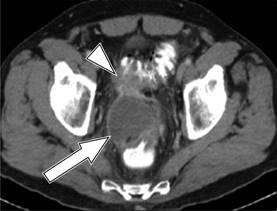

El estadio de la enfermedad en pacientes con diverticulitis a menudo se determina mediante el sistema de clasificación de Hinchey modificada por Wasvary (1999) y los hallazgos tomográficos por Kaiser a los que se incorporan los resultados de imagen (Cuadro 1 y Figura 1),16 los cuales comprenden desde el estadio 0 hasta el IV, en los que el estadio 0 (Figura 2) nos habla de una diverticulitis clínicamente moderada. El estadio I se divide en dos el IA (Figura 3) que se refiere a la inflamación pericólica limitada sin absceso y el estadio IB (Figura 4) en el que además de inflamación hay absceso adyacente a la zona de inflamación. En el estadio II (Figura 5) se encuentra el absceso pélvico, retroperitoneal o a distancia. En el estadio III (Figura 6) evoluciona a peritonitis generalizada sin comunicación a la luz intestinal y en el estadio IV hay peritonitis fecaloide con comunicación a la luz intestinal.17,18

Figura 6: Diverticulitis grado III: TC con contraste en corte axial muestra aire libre (cabeza de flecha) con presencia de líquido (flecha) en colon sigmoides.